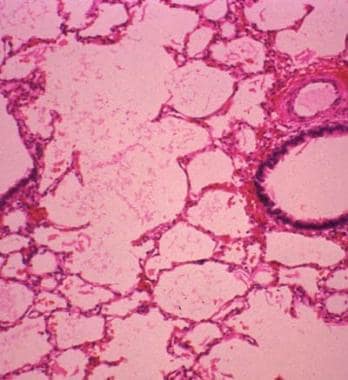

Lobar collapse demystified: the chest radiograph with CT correlation | Postgraduate Medical Journal  Lobar Pneumonia at 20x Magnification | Nikonâs MicroscopyU

Lobar Pneumonia at 20x Magnification | Nikonâs MicroscopyU  Lobar TV - Lobar Incorporated

Lobar Pneumonia, Grey Hepatic Phase Stock Photo - Image of grey, microscope: 130407010  Lobar holoprosencephaly | Radiology Case | Radiopaedia.org

lobar pneumonia - Liberal Dictionary  Lobar hemorrhage | Radiology Reference Article | Radiopaedia.org

Lobar Pneumonia vs Bronchopneumonia | eHealthStar  ENFISEMA LOBAR CONGENITO PDF

Lobar Pneumonia at 10x Magnification | MicroscopyU  Congenital Lobar Emphysema Article